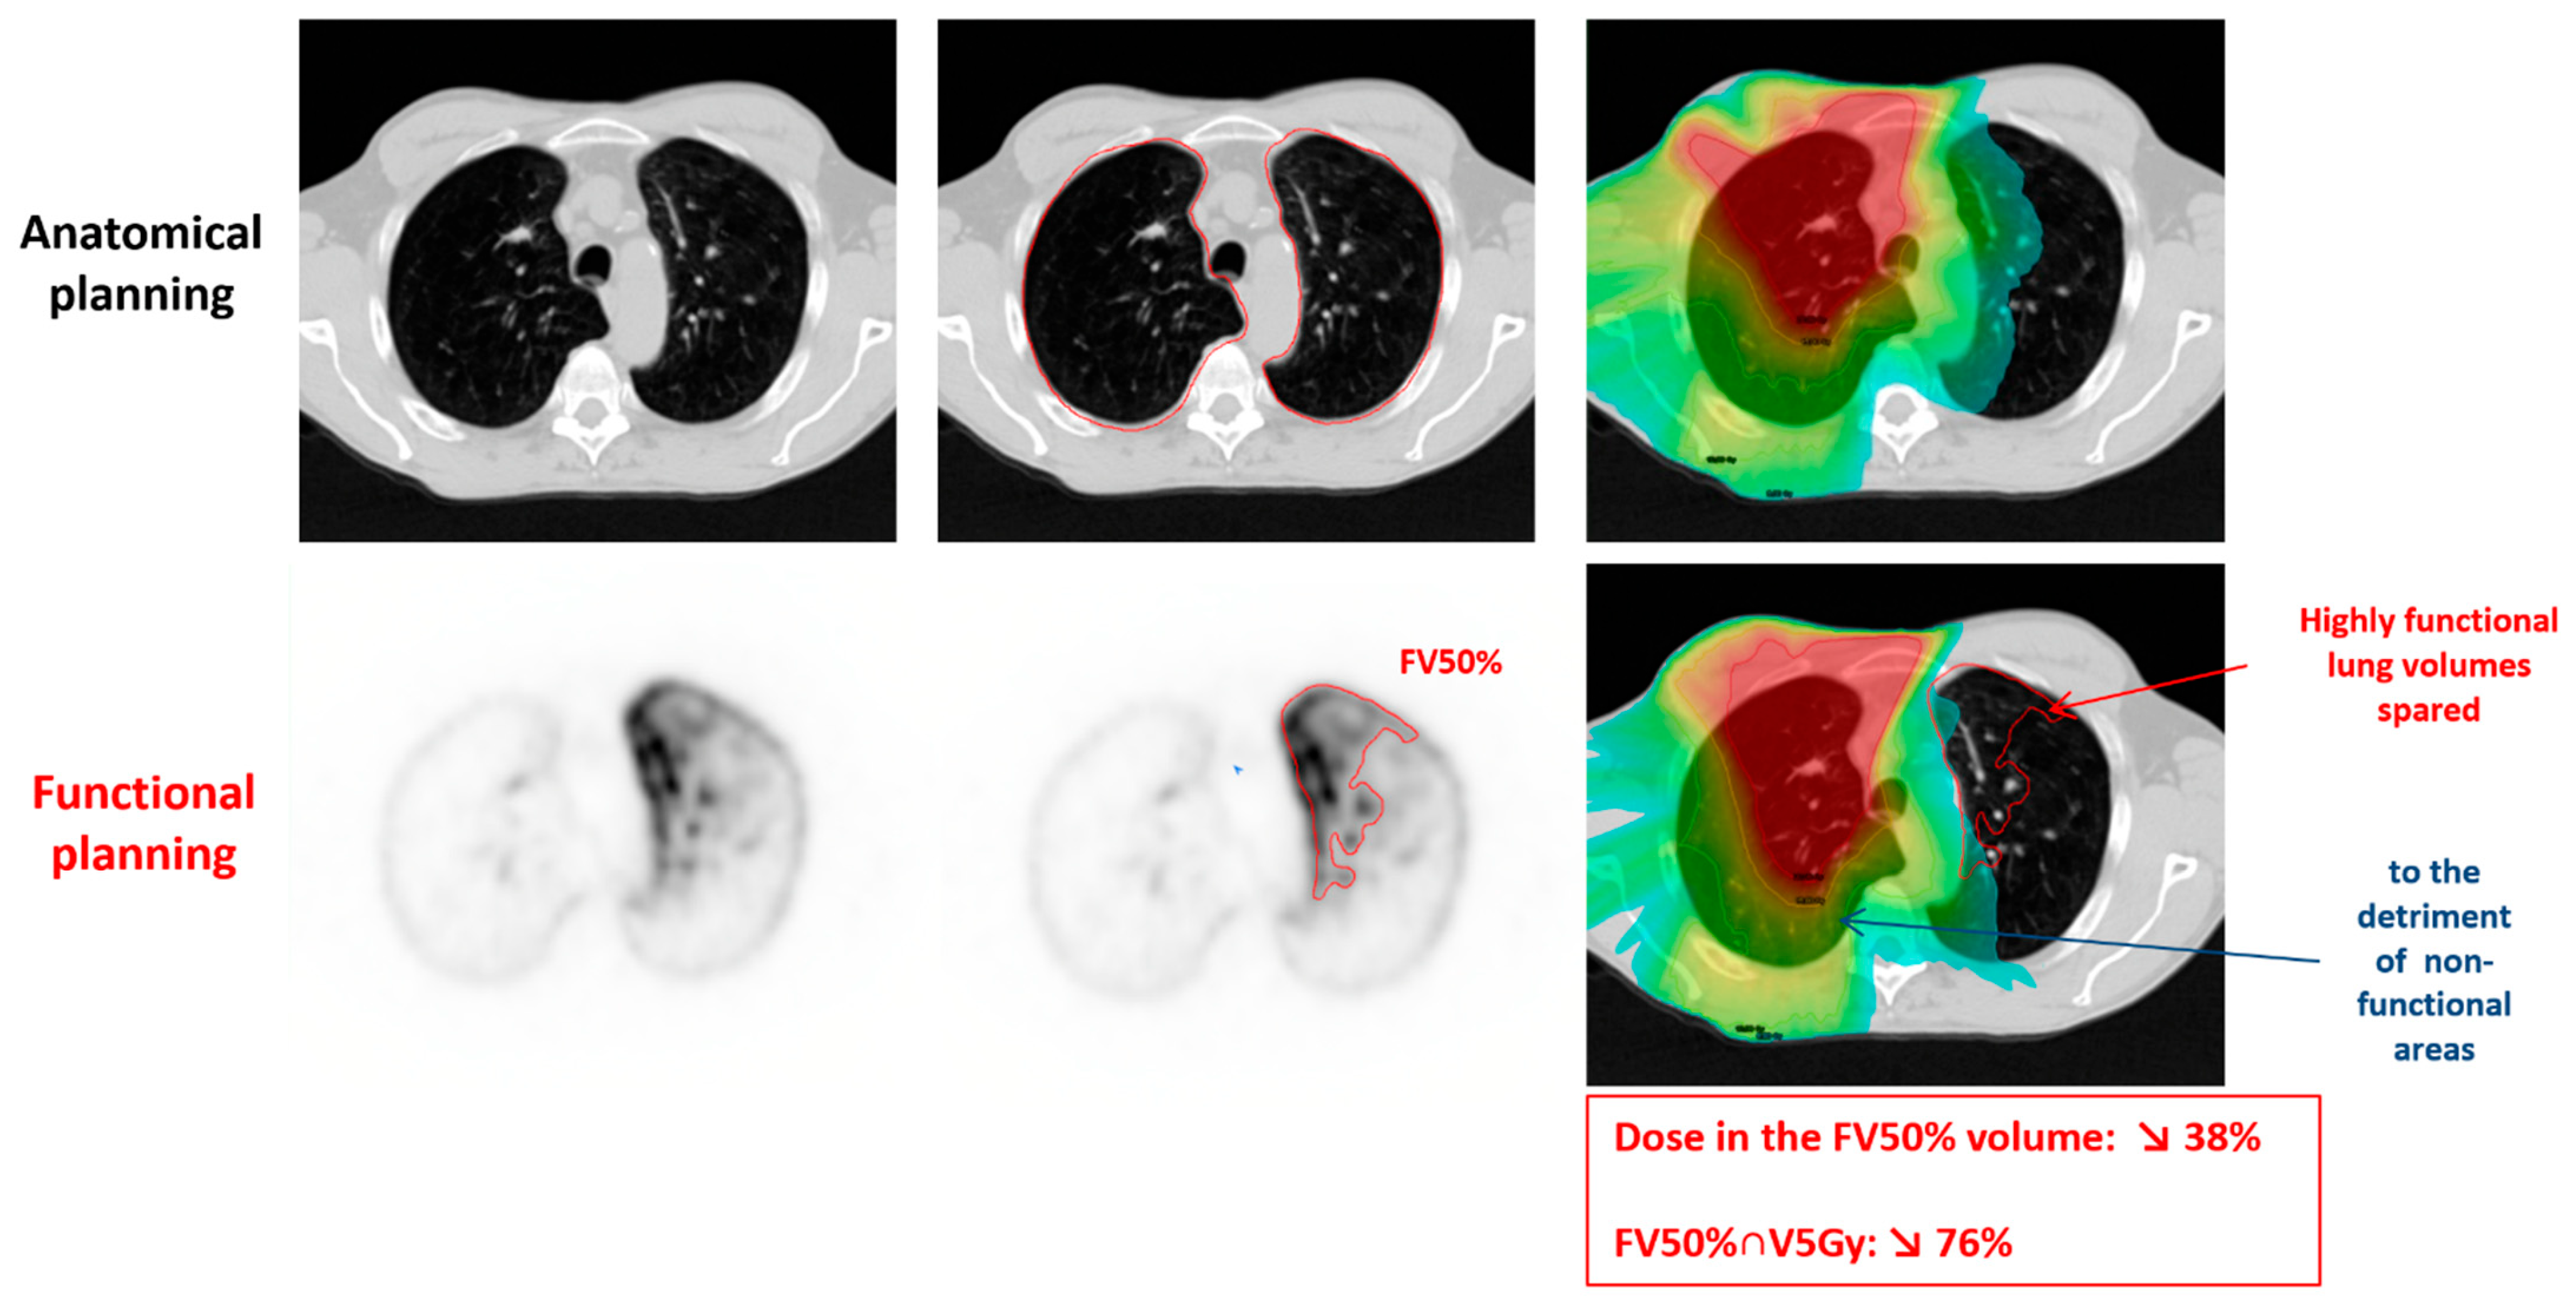

Figure 3 demonstrates a representative example of personalized SBRT lung planning and dosimetry guided by 68Ga-perfusion PET/CT imaging.

Figure 3.

Example of personalized lung SBRT planning and dosimetry based on 68Ga-perfusion PET/CT imaging. The first row shows the conventional anatomical planning based on CT imaging. The second row shows functional planning based on 68Ga-perfusion PET/CT imaging. The anatomical planning included highly functional lung volumes in the left upper lobe. By incorporating an additional “functional lung volume constraint” to the lung FV50% in addition to the standard constraints in SBRT planning, it was possible to spare this highly functional volume in the left upper lobe, to the detriment of the posterior aspect of the right upper lobe which was non-functional. This resulted in a 38% decrease of the dose in the FV50% volume and a 76% decrease of the FV50% volume receiving more than 5Gy.